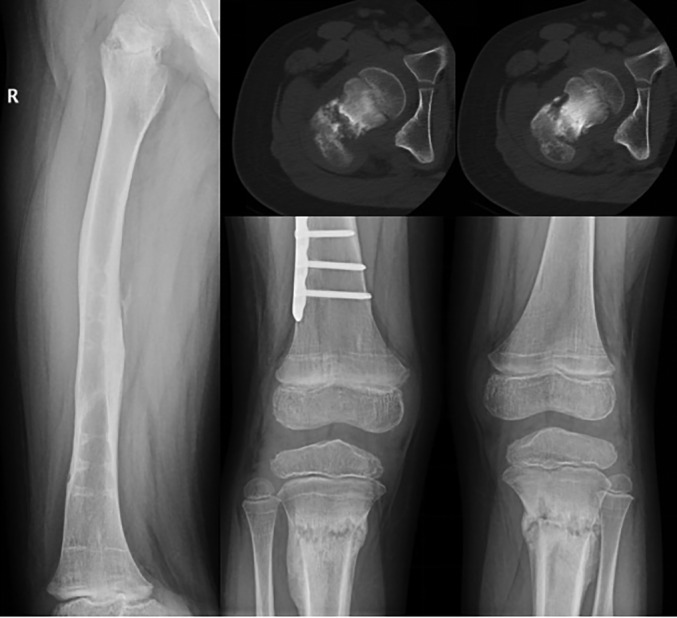

Figure 1.

(A,B) Old fracture of the middle part of the right fibula, eschar formation (X‐ray positive and lateral position). (C,D) Right middle and lower thigh fracture, spiral fracture line (X‐ray positive and lateral position). (E,F) Bilateral proximal tibia fractures, CT showed cavity formation in the bone marrow cavity. (G,H,I) Bilateral proximal tibia fractures, the fracture site showed a large number of eschar formation (X‐ray positive and lateral position). (J) The old fracture of the right thigh neck, the shortening of the neck of the thigh. (K) Old fracture of the middle part of the fibula on the right, scab formation.

We have a special case of a multiple‐fracture patient, male, born on 26 October 2011, Chinese, Han nationality. The child had a history of repeated and multiple lower extremity fractures which started at 5 years old (five times in 2 years, including six fractures in six parts). These fractures were usually accompanied with emotional instability, impatience and hyperactivity, biting fingers, and so on. According to the order of fracture, the fractures were in the middle part of the right fibula, the middle and lower segment of the right thigh, the bilateral upper tibia, the right neck of the thigh, and the middle part of the right fibula (Fig. 1, Table 1). There can be an obvious history of trauma or no history of trauma at the time of fracture. The fractures are mostly mild violent damage, and there may be temporary pain after injury.